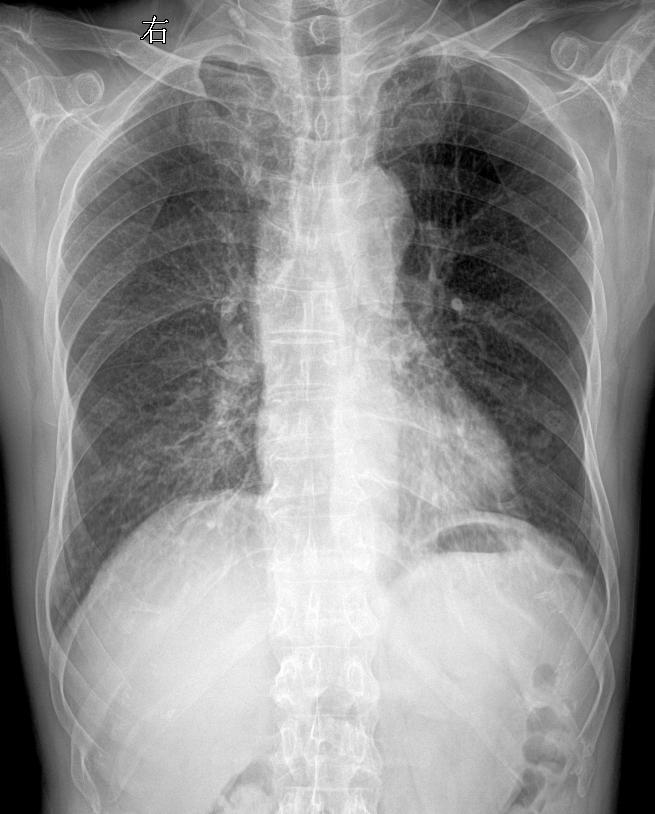

术后胸闷就诊 考虑什么?家银们

咳嗽胸闷就诊

又来一张,患者主诉:胸闷,咳痰

胸闷咳嗽就诊,考虑什么家人们?